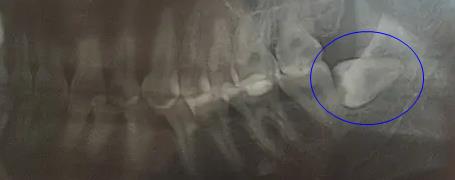

智齒拍片後情況

更何況智齒是牙齒排列末端的牙齒,鄰牙也隻有前麵的第二磨牙。即便是智齒生長位置不正,距離很近或者頂著鄰牙了,拔除智齒時醫生也會(hui) 盡量采用不傷(shang) 鄰牙的方法,把智齒切割為(wei) 幾個(ge) 部分再拔除,而不是整顆牙拔除。

難度大的智齒拔除方式